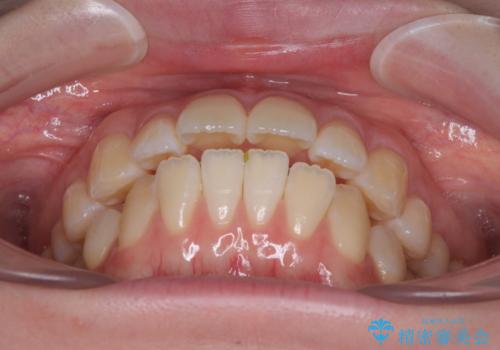

飛び出した前歯を引っ込める ワイヤー装置での抜歯矯正治療

- くちばしのように飛び出した前歯を気にして来院された患者様です。

上下左右の第一小臼歯4本を抜歯して、ワイヤー装置にて矯正治療を行うこととしました。

舌の突出癖により、口元が突出しているだけでなく、上下前歯が非接触となっておりました。

舌のトレーニングをしっかりと行っていただくことで、2年を切って治療を終えるとともに

、上下前歯を接触させることができました。